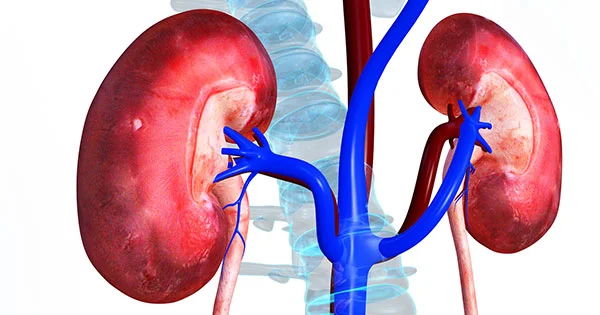

Diabetes is one of the most common systemic disease to affect the KIDNEY

Small blood vessels in the kidney filter out the waste products from the body. High blood pressure and high blood sugar can damage these vessels thereby they will not be able to do their functions effectively.